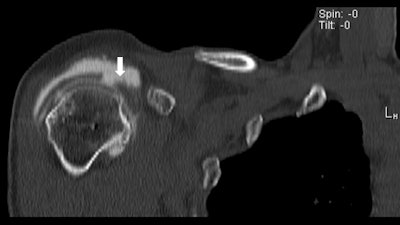

The increased use of metallic screws and other fixation devices to repair shoulder injuries is making CT a more effective imaging option than MRI for evaluating postoperative results.

In a comparison with conventional MRI and MR arthrography, CT detected additional pathology when the presence of metallic artifacts essentially precluded an assessment of the shoulder on MRI, according to study results presented at RSNA 2015.

While these metallic screws and fixation devices are MRI-compatible, "they all cause a degree of metallic artifact," said study author Dr. Thomas Magee, a principal owner at NeuroSkeletal Imaging of Florida. "In that regard, CT has been helpful in the diagnosis of labral tears or supraspinatus tendon tears in the postoperative shoulder."

In general, postoperative shoulder patients are often difficult to image due to scar tissue, metallic artifacts, and anatomic abnormalities. Thus, there is some debate over how to image a postoperative shoulder accurately, Magee said.